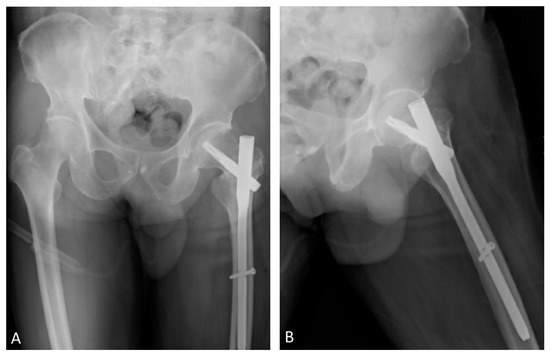

Teriparatide as an Effective Nonsurgical Treatment for a Patient with Basicervical Peritrochanteric Fracture Nonunion—A Case Report

The nonunion rate of surgically treated basicervical peritrochanteric fractures has been reported to be as high as 9%. Due to the high 1-year mortality rate following revision surgery, finding an effective nonsurgical treatment option is of interest. Over the last decade, numerous reports have been published that have suggested teriparatide as an effective treatment for certain types of fracture nonunion. However, the literature focused on teriparatide treatment for proximal femoral fracture nonunion is scanty. A 70-year-old man suffering from a left hip basicervical peritrochanteric fracture received cephalomedullary nail fixation. Nine months after the surgery, the patient still complained of left hip pain referring to the medial thigh with an antalgic limping gait. No sign of healing was noted for more than a consecutive 3 months of follow-up. Fracture nonunion was diagnosed and further confirmed by the computed tomography (CT). The patient preferred nonsurgical treatment after thorough discussion. He then received 4 months of subcutaneous teriparatide injections, 20 mcg daily. After less than 4 months of teriparatide treatment, a follow-up CT confirmed fracture union and the patient’s pain subsided. The patient also tolerated independent ambulation afterward. Teriparatide has been reported to be an effective treatment for certain types of fracture nonunion. Our case goes a step further to expand its possible application for basicervical peritrochanteric fracture nonunion. However, further larger scale studies are needed to confirm its efficacy. Full article

Show Figures

Figure 1